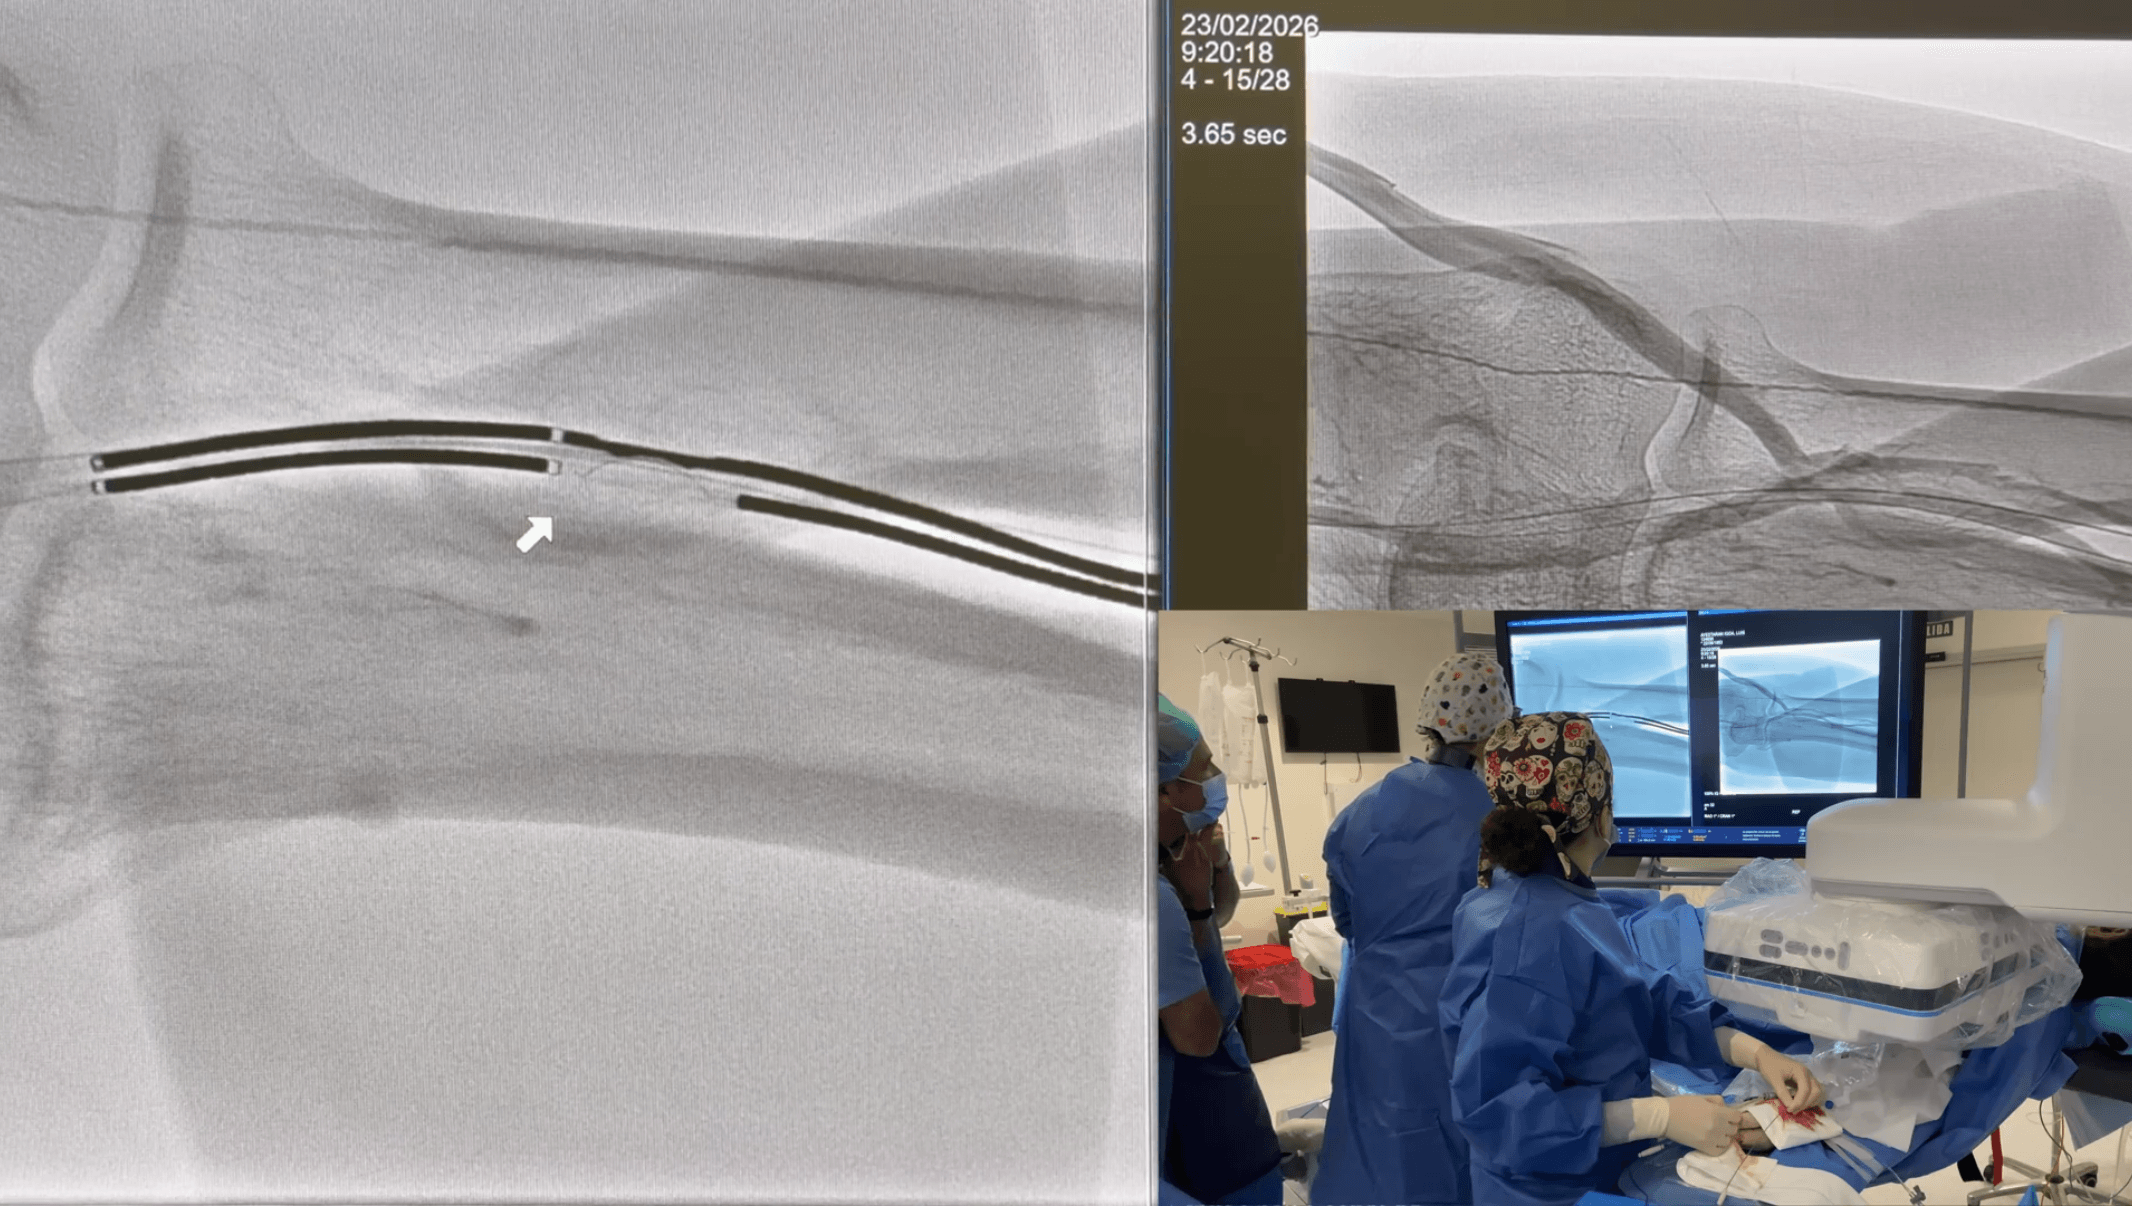

Aproximación arteriovenosa

Uno de los momentos críticos es la aproximación controlada entre arteria y vena. Mediante sistemas específicos, se consigue colocar ambos dispositivos enfrentados en puntos anatómicamente favorables.

El Dr. Iñigo Insausti enfatiza la importancia de confirmar en múltiples proyecciones la correcta posición antes de proceder, evitando errores de alineación que comprometerían la fístula.

Creación de la anastomosis

Se realiza la conexión arteriovenosa mediante energía controlada o sistemas mecánicos, generando un paso de flujo inmediato entre ambas estructuras.

- Confirmar flujo inmediato mediante angiografía

Tras la creación de la EndoFAV, se realiza una angiografía de control para verificar:

- Flujo adecuado

- Ausencia de extravasación

- Correcta dirección del flujo venoso